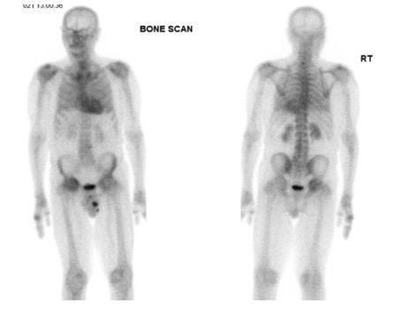

This is an online published case report of a patient who underwent an MDP bone scan for metastatic workup. The scan was negative for the mother’s reason. However, mild cardiac uptake was incidentally detected. Later, a PYP scan was performed to confirm the diagnosis of CA, which resulted in intense cardiac uptake with the final diagnosis of ATTR CA. (Figure 9)

Figure 9 Demonstrating MDP bone scan of a patient undergoing metastatic work up, which was negative metastatic disease but raised suspicion of CA due to mild uptake in the cardiac, PYP was done after MDP bone scan to confirmed the diagnosis of CA. Published by Fathala, 202051

(A) MDP bone scan for metastatic work up, showing normal bone and mild uptake in cardiac.

(B) PYP bone scan for suspected cardiac amyloidosis, showing normal bone and intense cardiac uptake.